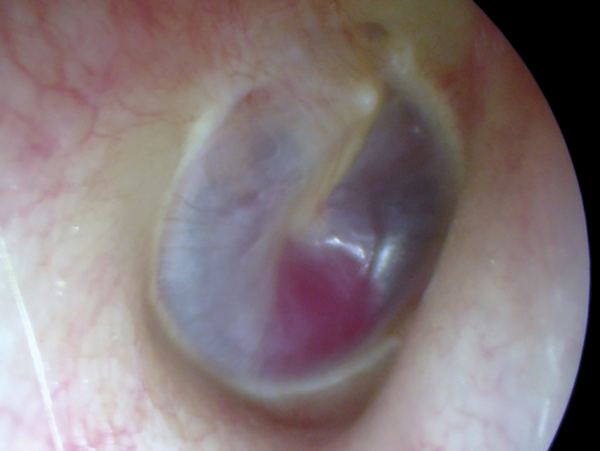

Figure 2: Gadolinium enhanced MRI scan showing a left vestibular schwannoma.

Imaging studies are not indicated unless tinnitus is unilateral, pulsatile, or there is asymmetric hearing loss or focal neurological abnormalities. Patients who report experiencing unilateral subjective tinnitus with or without hearing loss should undergo gadolinium enhanced MRI in order to exclude any cochlear or retrocochlear abnormality (Figure 2). Patients with pulsatile tinnitus should undergo CT angiography.